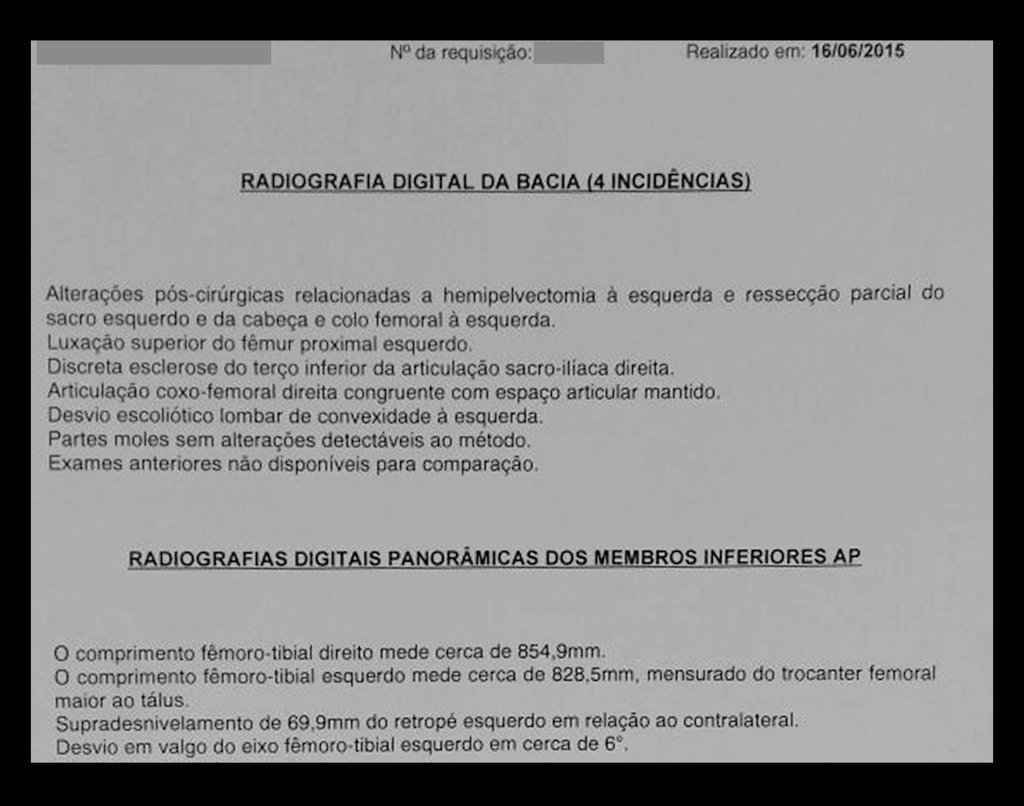

Imediatamente após a cirurgia, radiografias confirmaram a ressecção completa da hemipelve esquerda, juntamente com o colo femoral e o complexo capsulo-ligamentar da articulação do quadril esquerdo.

Avaliação Pós-Operatória a Longo Prazo

- Um ano pós-operatório: Paciente apresentava carga total com auxílio de muletas, boa função e flexão dos joelhos.

- Um ano e seis meses pós-operatório: Boa adaptação e função do membro inferior esquerdo (MIE), apesar do encurtamento compensado por calçado especial.

- Dois anos pós-operatório: RM sem sinais de recidiva, bom aspecto local.

- Três anos pós-operatório: Paciente sem sinais de recidiva, bom resultado funcional e cosmético, compensação com calçado.

- Quatro anos pós-operatório: Estabilidade da discrepância do MIE, excelente recuperação funcional.

- Doze anos e três meses pós-operatório: Paciente exibiu uma vida sem limitações significativas, superando o déficit funcional e exercendo atividades diárias com desenvoltura.